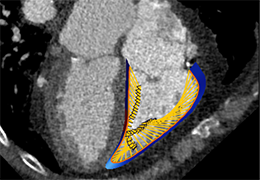

View X-Ray CT & MRI Scans Fast and Easily

Designed for surgeons, Pro Surgical 3D makes it easy to view patient scans quickly. Pro Surgical 3D facilitates the optimal 3D treatment and assessment workflows based on X-ray CT and MRI scans – and best of all, it’s FREE!

Performs 3D reconstruction and volume rendering.

Instant and interactive surface extraction and export to STL and PLY formats.

Side-by-side comparative assessment for pre- and post-operative scans.